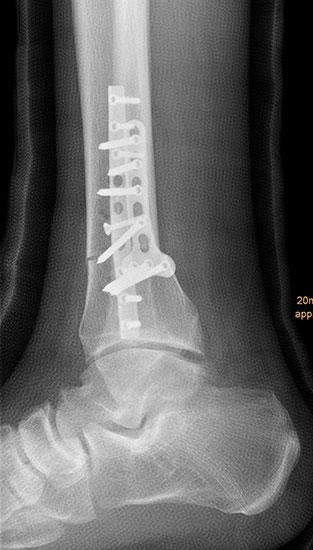

Auch hier wird die Korrektur im CORA (Center oft Rotation and Angulation) durchgeführt. Primär werden intraoperativ unter Bildwandler Kontrolle Kirschner Drähte als Sägelehre konvergierend eingebracht. Dann wird der geplante medialbasige Keil mit der oszillierenden Säge entfernt. Die laterale Kortikalis sollte geschont werden, sie dient als Drehpunkt für die Osteotomie. Die Osteosynthese kann dann im Sinne einer Zuggurtung ein besonders stabiles Konstrukt bilden. Liegen mehrdimensionale Deformitäten vor, die eine Korrektur in Translations- und Rotationsebene erfordern, ist eine Durchtrennung der lateralen Kortikalis notwendig, ebenso bei ausgedehnten Korrekturen mit Keilhöhen über 10mm 218.

Wir benutzen zur Osteosynthese 3,5 mm LCP T-Platten. In der intraoperativen Röntgenkontrolle kann im seitlichen Bild die Zentrierung des Talus überprüft werden, und ggf. durch eine milde extendierende oder flektierende Korrekturkomponente verbessert werden 18. Eine begleitende Deformität der Fibula korrigieren wir üblicherweise mit einer z-förmigen Osteotomie die wir mit einem 1/3 Rohrplättchen sowie einer Zugschraube sichern 18.

Insbesondere bei in Valgusposition fehlverheilten OSG Frakturen nimmt die Fibula eine Schlüsselposition zur korrekten Einstellung des Gelenkes ein 1920. Verheilt die Fibula in Verkürzung, führt dies zu einer Lateralisation des Talus. Eine korrigierende Verlängerungsosteotomie ist dann zur Rezentrierung des Gelenkes essentiell 2122. Auch die umfassenden biomechanischen Arbeiten von Stufkens und Kollegen unterstreicht die essentielle Bedeutung der Fibula bei Deformitäten des oberen Sprunggelenks in der Fronalebene 23.